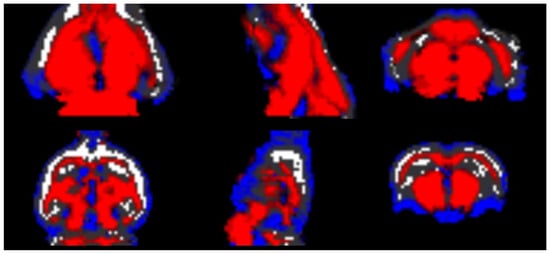

| Tests | Test1 | Test2 | Test3 | Test4 | Test5 | Test6 | Test7 | Test8 | Test9 |

|---|---|---|---|---|---|---|---|---|---|

| Data sets | Dr174 | Dr174 Ds87 | Dr174 Ds174 | Dr174 Ds261 | Dr174 Ds348 | Ds174 | Ds348 | Dr87 Ds174 | Dr87 Ds348 |

| Global | 0.8969 | 0.9138 | 0.9083 | 0.9078 | 0.9141 | 0.8238 | 0.7646 | 0.8979 | 0.8259 |

| GM | 0.9381 | 0.9419 | 0.9384 | 0.9376 | 0.9412 | 0.8863 | 0.8586 | 0.9316 | 0.8863 |

| WM | 0.8969 | 0.9077 | 0.9037 | 0.9014 | 0.9098 | 0.8202 | 0.7262 | 0.8897 | 0.8301 |

| CSF | 0.7468 | 0.8232 | 0.8098 | 0.8170 | 0.8180 | 0.6095 | 0.4418 | 0.7442 | 0.6273 |